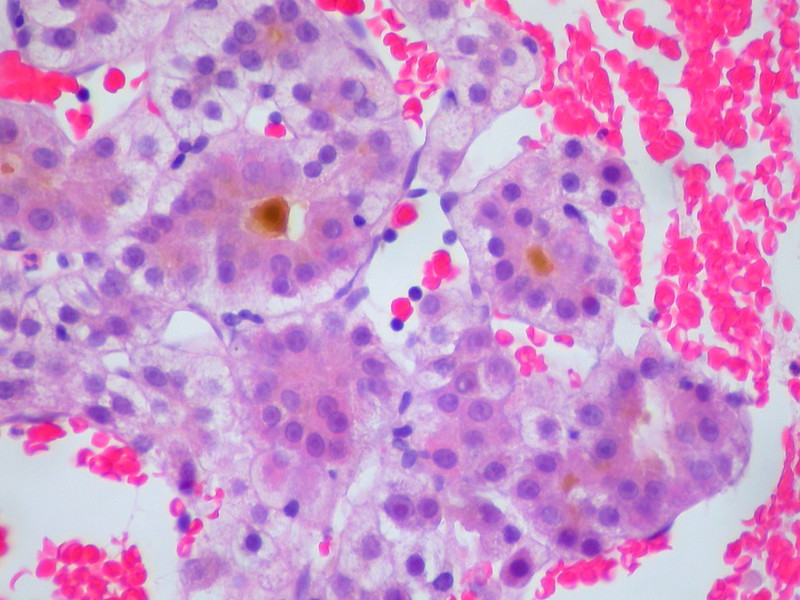

Hemochromatosis

Excess bodily iron causes hemosiderosis, which can cause organ damage and tissue deposition in the condition known as hemochromatosis.

Liver histology shows that the hepatocytes have accumulated brown pigment.

The brown pigment is lipofuscin, a byproduct of the turnover, wear and tear, and peroxidized lipids.

Prussian blue stain differentiates iron from lipofuscin.

There is an elevated risk of hepatocellular carcinoma in hemochromatosis.